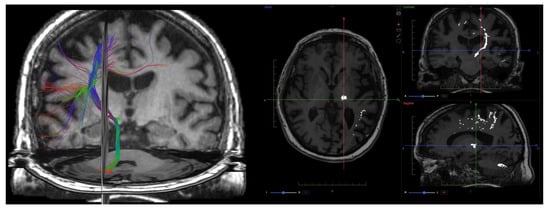

9. Diffusion Imaging (DWI, DTI, DKI)

9.1. Physics and Signal Model

9.2. Acquisition and Key Parameters

9.3. Outputs and Units

- Fractional anisotropy (FA): degree of diffusion directionality,

- Mean diffusivity (MD): average diffusivity, equivalent to ADC but derived from tensor data,

- Axial diffusivity (AD): diffusion parallel to axons,

9.4. Clinical Applications

9.5. Validation and Repeatability

9.6. Emerging Techniques and Integration